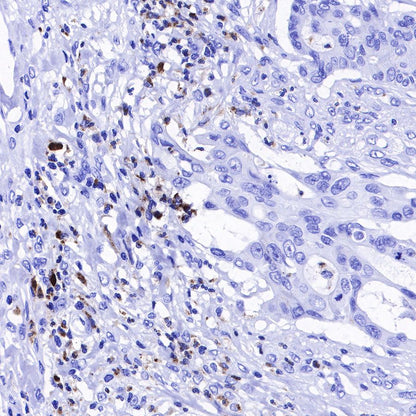

Immunohistochemistry

IHC shows positive staining in paraffin-embedded human liver. Anti-Lysozyme antibody was used at 1/100 dilution, followed by a HRP Polymer for Mouse & Rabbit IgG (ready to use). Counterstained with hematoxylin. Heat mediated antigen retrieval with Tris/EDTA buffer pH9.0 was performed before commencing with IHC staining protocol.

IHC shows positive staining in paraffin-embedded human tonsil. Anti-Lysozyme antibody was used at 1/100 dilution, followed by a HRP Polymer for Mouse & Rabbit IgG (ready to use). Counterstained with hematoxylin. Heat mediated antigen retrieval with Tris/EDTA buffer pH9.0 was performed before commencing with IHC staining protocol.